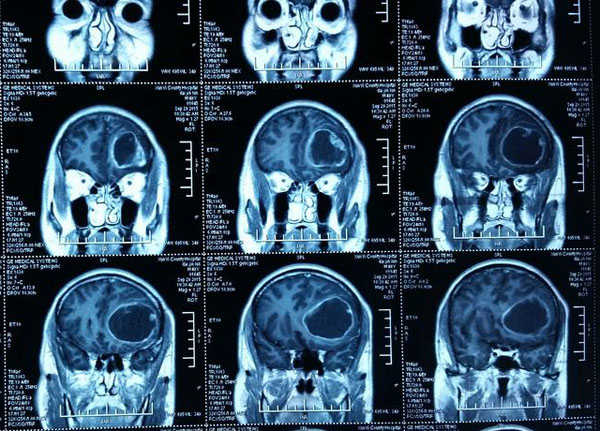

首先,依据患者出现症状。例如头痛(通常是早晨头痛,通常伴有恶心)或神经症状。症状可能包括局灶性或全身性癫痫发作,单手无力,手臂或腿部,双重视力,无法书写或拿着咖啡杯,难以记忆或说话等。当患者向医生表述时,获得的MRI显示肿块。

在扫描中发现异常肿块后,根据扫描的外观以及患者所显示的体征和症状,进行活组织检查/或切除大部分肿瘤。然后病理学家检查组织并诊断。可能对患者的病史,身体检查结果(体征)和扫描的外观有什么类型的肿瘤有相当强烈的怀疑,但在显微镜下检查是确定诊断的唯一方法。